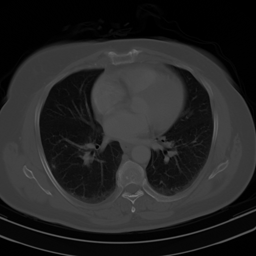

Fig. 2 presents an example of this result. In this figure, the ‘Mickey Mouse’ detail , whereas the ‘Thumb’ detail has relatively large measurements, i.e., . The NN is trained to recover the image . As a result, it incorrectly transfers the detail , while the detail is handled correctly (i.e., it is not transferred). Fig. 4 shows another example of this effect. In this case, is a subsampled Radon transform, which models a CT imaging scenario. Here, the NN is trained to recover the detail image , and as a result, it incorrectly transfer the detail when recovering the detail-free image .

A.4 Fig. 4

In Fig. 4, we trained a NN to reconstruct CT images from Radon measurements. For the sampling operator, we used MATLAB’s implementation of the Radon transform, and sampled 50 equally spaced angles. The choice of considering 50 angles is inspired by the seminal work of Jin, McCann, Froustey & Unser in [40]. As we considered images with dimensions , the sampling operator had dimensions and .

In this experiment we used the 100 CT images from the cancer imaging archive [5, 20] that have been made available at kaggle.com (See: https://www.kaggle.com/datasets/kmader/siim-medical-images/). Due to the small size of this dataset, we trained the NN in two stages. In the first stage, we pretrained the NN on the 25000 ellipses images used to train the NNs in Fig. 5. Then we fine-tuned the NN on 95 CT images from the dataset mentioned above. Among the 95 images used for training was the image , where is the “SIAM” detail seen in the image. The clean image was not part of the training data. The detail was designed such that . Specifically, we computed as , where is the identity matrix, and is a black image with the “SIAM” text feature.

The architecture of the trained NN can be written as , where is a learnable U-Net and is the matrix of a (non-learnable) Filtered Backprojection (FBP) with a “Ram-Lak”-filter. The “Ram-Lak”-filter was chosen as it is the default filter in MATLAB. We trained the network for 60 epochs in the pretaining phase and for 520 epochs in the fine-tuning phase. We used a larger number of epochs in the fine-tuning phase than in the pretraining phase, as the amount of training data was substantially smaller in the fine-tuning phase. During all training epochs we used a mean-squared-error loss function and noiseless measurements.